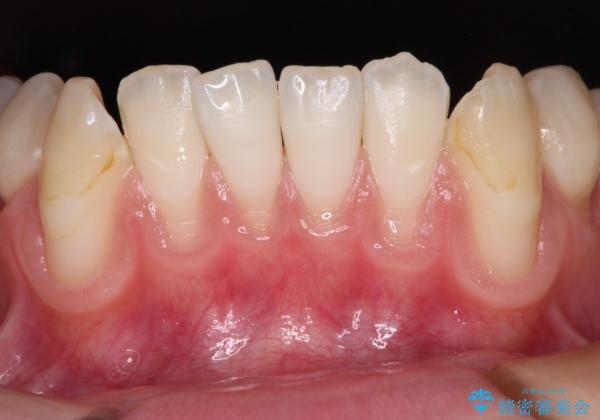

- 歯肉退縮による知覚過敏を気にして来院された患者様です。

診察したところ、知覚過敏をむし歯と勘違いし、一生懸命磨いたことで横縞模様ができるほどでした。

歯肉退縮に対して、上顎からの結合組織移植術(CTG)により、歯根の被覆を行うとともに、歯肉の厚みを増すことで将来の退縮リスクを抑制することとしました。